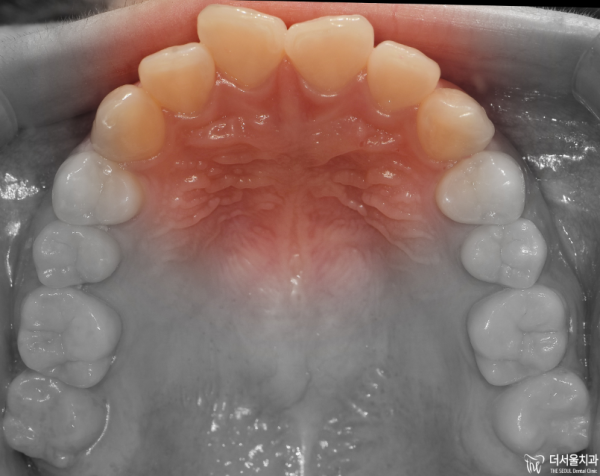

이렇게 교합면을 보면 앞니들이 위 아래 모두 삐뚤빼뚤한

총생을 보이고 있습니다.